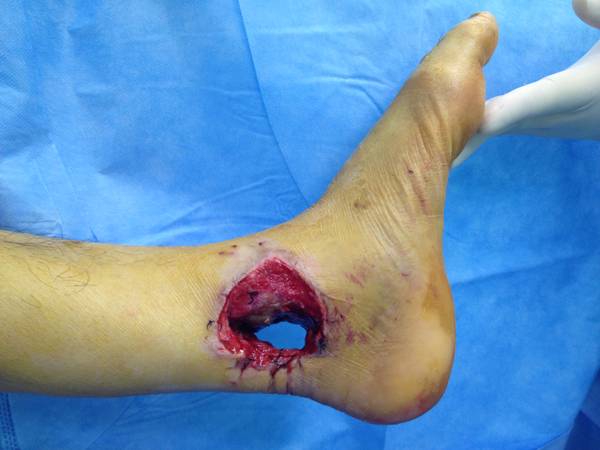

男性患者,35岁,机械伤致左踝上组织贯通,部分肌腱血管神经缺损.行肌腱\血管神经的吻合.

损伤情况

损伤